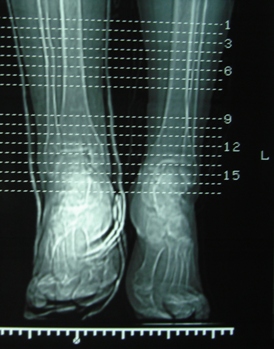

Продолжая тему представляю данные КТ нашей пациентки.

Имя     : КТ-линейка.JPG

Тип     : image/jpeg

Размер  : 66868 байтов

Url     : http://weborto.net:8080/pipermail/ortho/attachments/20091107/a87a6ebe/attachment-0005.jpeg